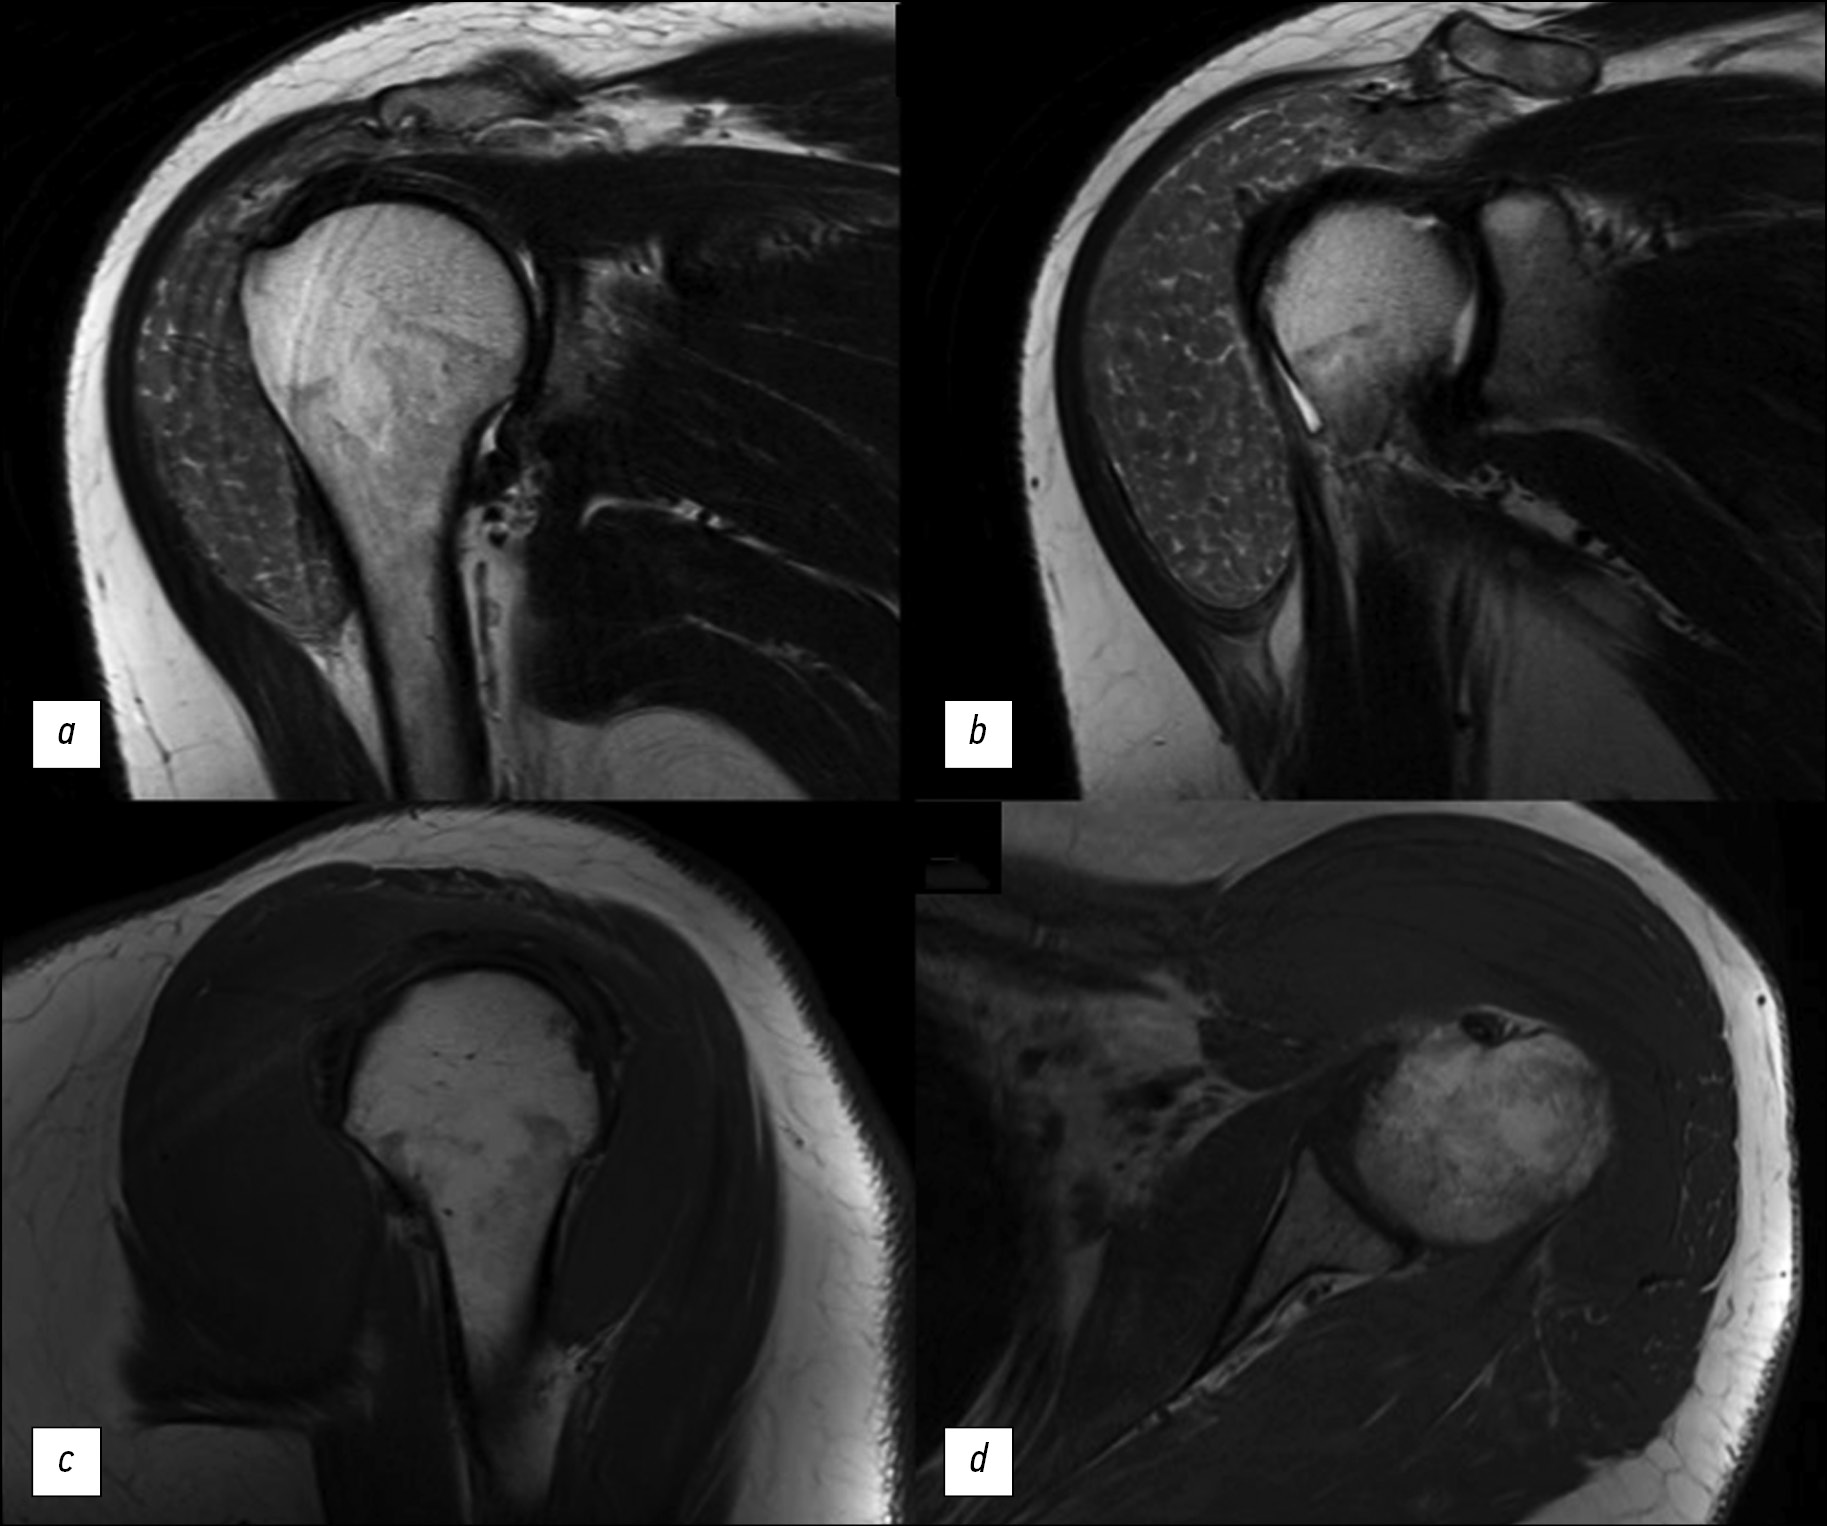

“Rice bodies” symptoms on magnetic resonance imaging of the shoulder in a patient with rheumatoid arthritis

The “rice bodies” symptom on magnetic resonance imaging of the shoulder joint in patients with rheumatoid arthritis is a rare but specific finding characterized by the presence of multiple small, round, rice-grain-like structures in the synovial fluid of the joint, synovial pouches, or sheaths. The etiology of the “rice bodies” is still not fully understood. They are suggested as the result of microinfarcts of the synovial membrane in patients with rheumatoid arthritis or other inflammatory joint diseases. Clinically, the “rice bodies” symptom may cause pain, but not in every case. Among radiological diagnostic methods, magnetic resonance imaging is the leading method for the detection of rice bodies. This article presents a clinical case of “rice bodies” symptoms diagnosed by magnetic resonance imaging in a patient with a long history of rheumatoid arthritis who presented with a painless enlargement in the left shoulder. Computed tomography and magnetic resonance imaging of the left shoulder could detect “rice bodies” as a manifestation of an underlying disease and determine further treatment techniques.

616-624